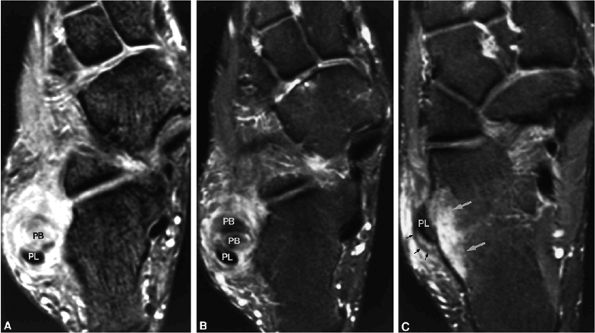

FIGURE 5.158 ● (A) Color illustration of a peroneus brevis partial tear. Tenosynovitis (paratenonitis) with tendinosis including longitudinal tears and tendinosis of the peroneus brevis usually occurs at the level of the fibular groove at the distal lateral malleolus. Longitudinal tendon tear is shown on sagittal FS PD FSE (B) and axial FS PD FSE (C, D) images. The resultant two subtendons distal to the lateral malleolus are shown in (D).

|